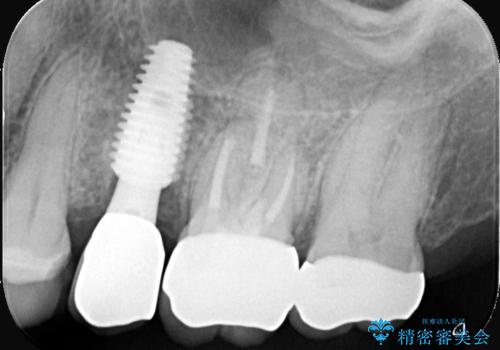

- 患者様は、左上第一小臼歯の垂直性歯根破折が確認され、抜歯が必要となりました。本来、抜歯即時埋入を適用できるケースでしたが、患者様のご都合によりブリッジとインプラントで一度悩まれるとのことで待時埋入となりました。治療計画では、上顎の骨の状態を慎重に評価し、デンサーバーを用いてドリリングを行うことで、上顎洞粘膜を傷つけずにインプラントを埋入する方法を選択しました。埋入後の安定を確保するため、術後の経過観察を慎重に行います。

待時埋入では、抜歯後に骨の再生を待つ必要があり、即時埋入に比べて治療期間が長くなります。しかし、デンサーバーを使用した精密なドリリングによって、上顎洞粘膜を破らずにインプラントを埋入することができ、術後の合併症リスクを最小限に抑えることができました。インプラント埋入後は、骨との結合を待ちながらしっかりとしたケアと定期的な検診を行い、最終的な補綴物の装着に備えます。